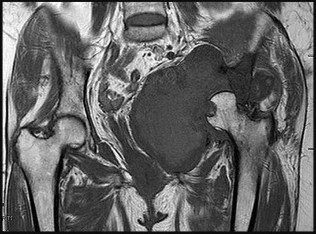

A 12-year-old obese male presents with left groin pain and an altered gait. Based on the presumed diagnosis of slipped capital femoral epiphysis (SCFE) shown in the representative radiograph, which of the following is the primary blood supply to the femoral head that is at highest risk for iatrogenic injury during percutaneous in situ pinning if the pin is placed in the posterosuperior quadrant?

Options:

Correct Answer: Posterosuperior retinacular vessels from the medial circumflex femoral artery

Explanation:

The primary blood supply to the capital femoral epiphysis in children over the age of 3 is the posterosuperior retinacular vessels (lateral epiphyseal artery), which are terminal branches of the medial circumflex femoral artery (MCFA). During in situ pinning for SCFE, placement of the pin in the posterosuperior quadrant of the femoral neck/head places these extracapsular vessels at extreme risk of injury, potentially leading to avascular necrosis (AVN). Pins should ideally be placed in the center-center position to minimize this risk.